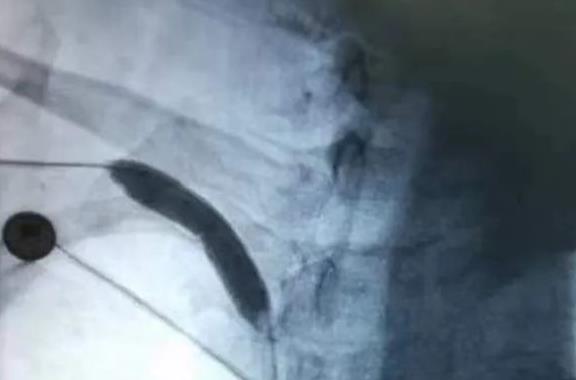

2023年4月19日,红河州第三人民医院介入外科,面对患者右上肢桡动脉严重闭塞的危急情况下,连夜实施急诊手术,成功开展首例上肢动脉闭塞取栓术,顺利为患者保肢并解除痛苦。 60岁的陈大伯2023年4月18日22:00诉右上肢疼痛、麻木,经值班医生孙春权查看患者后,发现患者右上肢冰凉、末梢发绀,右侧桡动脉不能触及。经右上肢CT血管造影、头颅CT平扫等急诊检查后,结果显示右上肢动脉闭塞。孙医生考虑到患者右上肢假若长时间供血阻断,会造成肢体坏死,从而截肢。随即将该情况告知了下班回家的副主任刘海川,刘医生说道,该疾病发展迅速,随时有血栓脱落,堵塞重要血管等可能,死亡率较高,必须立即急诊手术,立即从开远家中,匆匆赶往个旧。